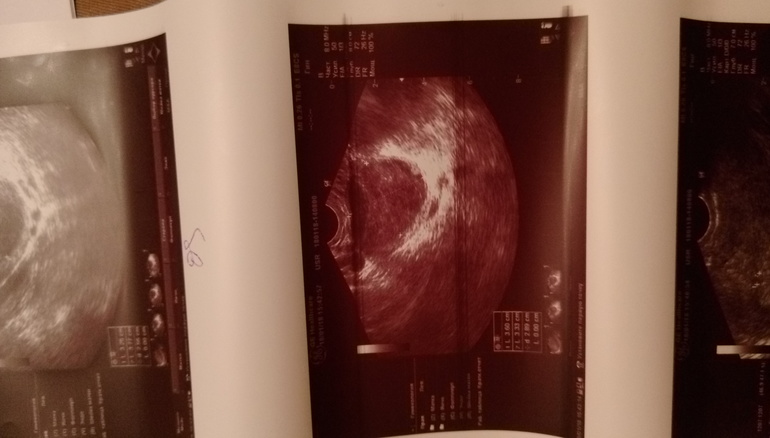

Дорогие девочки, сегодня 18 дц пошла я посмотреть была ли О. Хотя я ее на 14 дц поймала тестами, но так сказать подтвердить. А все так хорошо начиналось... Блин... сделала узи сегодня 2 раза, т.к. первое меня не устроило)))) мало что было понятно. Так вот что имеем... Киста жт (откуда взялась), на одном узи 22 мм на другом 30 с чем-то. Жидкость на одном есть, на другом нет((( Эндик на одном 12 мм, на другом 10 . Что вообще происходит кому верить? Возможна ли Б при таком узи, было активное планирование. И кто вообще с этим сталкивался. Я в шоке. Помогите советом. Фото узи под кат

Это второе узи! С первого фотки не брала))) они за отдельную плату!